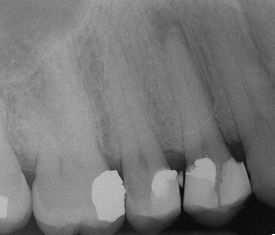

The excess restorative material that exceeds the natural contours of restored teeth, such as these, are termed "overhangs", and serve to trap microbic plaque, potentially leading to localized periodontitis.